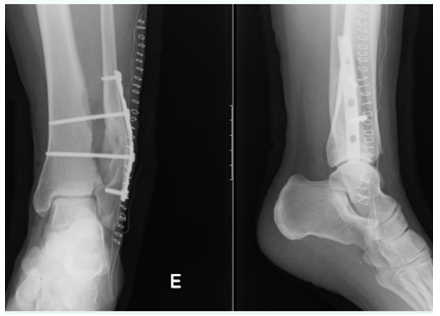

She was submitted to lesion excision and osteosynthesis with syndesmosis tibio-peroneal and fibula stabilization with plate and 2 trans-syndesmotic screws (Figure 4).

Figure 4 X-Ray post-excision of the lesion demonstrating osteosynthesis with plate and screws.

Histopathological examination confirmed the diagnosis of osteochondroma. At 2 months after surgery it was performed the extraction of two trans- syndesmotic screws (Figure 5), and after 18 months it was removed all material of osteosynthesis (Figure 6).

Figure 5 X-Ray after removing two trans-syndesmotic screws.